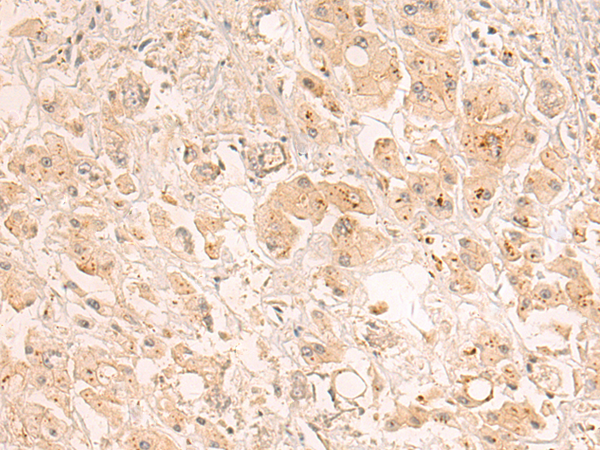

IHC positive control: |

Human lung cancer |

IHC Recommend dilution: |

20-100 |